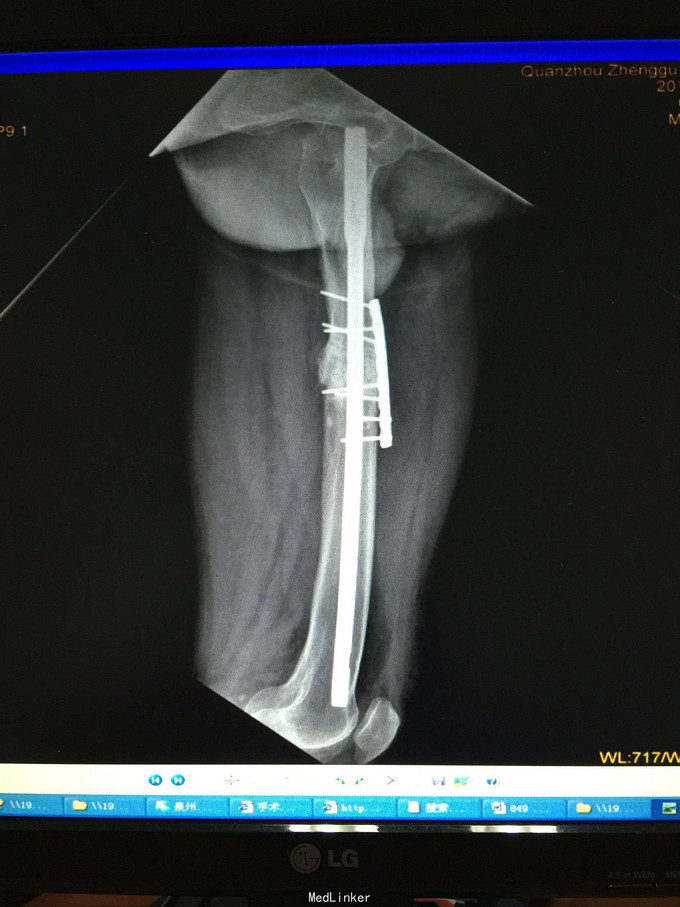

诊断:左股骨中上段骨折术后骨不连 处理:左股骨骨折术后骨不连断端清理+防旋钢板内固定+取髂骨植骨术

术后半年 讨论 考虑股骨中上段骨折 应力集中 近段一枚螺钉稳定性不够?